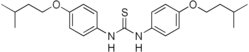

Thiocarlide

Thiocarlide (or tiocarlide or isoxyl) is a thiourea drug used in the treatment of tuberculosis, inhibiting synthesis of oleic acid and tuberculostearic acid.[1]

| Formula | C23H32N2O2S |

| Molar mass | 400.58 g·mol−1 |

SMILES

InChI